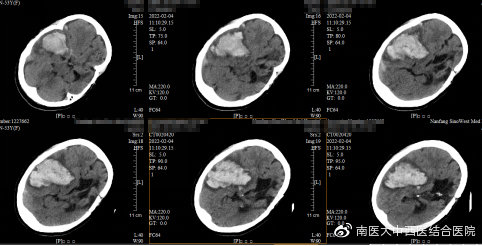

血肿清除术前CT